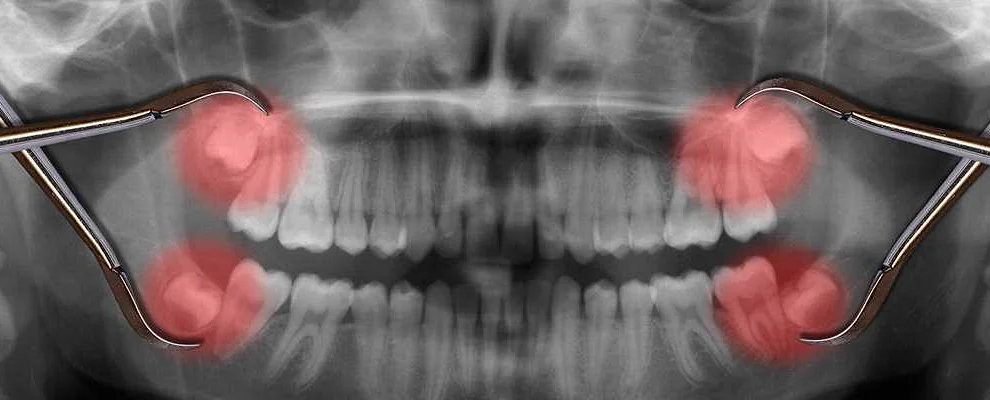

- сам врач или медсестра делает обезболивающие уколы в десну, обычно с нескольких сторон. Эффект анестезии наступает не сразу, несколько минут надо подождать. Время ожидания зависит от вида препарата, от индивидуальных особенностей организма;

- убедившись, что пациент не чувствует боли в области десны, врач слегка расшатывает зуб, ухватив его специальными щипцами, и аккуратно вынимает его.

- проведение сложной операции удаления зуба мудрости;

- аномальное месторасположение зуба, который удаляется;